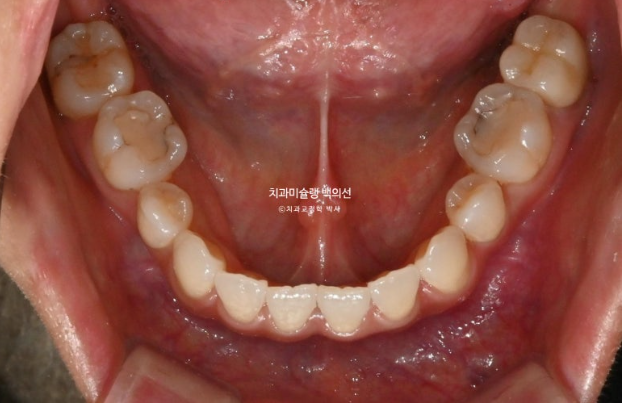

25년 2월 교정치료를 위해 온 환자분입니다.

오래 전 발치교정을 했는데 유지관리 단계에서 다시 틀어져 버렸습니다.

재교정을 해서 고치고 싶은 것은 튀어나온 위 앞니와 아래앞니의 블랙트라이앵글

앞니 하나가 들려있어요.

중절치 하나가 많이 나와있습니다.

아랫니도 약간의 배열 불규칙이 보입니다.